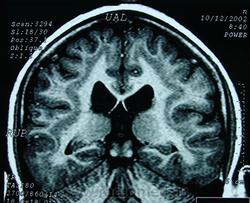

ГМ. Гетеротопии 1. Синдром «двойной коры» (Duplo córtex). +

Гетеротопии. Синдром «двойной коры» (Duplo córtex).

Наиболее частым вариантом миграционных нарушений является гетеротопия - скопление нейронов, остановившихся в различных аномальных местах на пути следования к коре головного мозга. Такая остановка происходит не позже 5-го месяца внутриутробного развития. Изолированный участок узловатой массы называется «гетеротопион». В настоящее время описаны следующие варианты гетеротопии:

- субэпендимальная нодулярная (узелковая) гетеротопия;

- ленточная (слоистая, ламинарная) гетеротопия;

- изолированная (одиночная) гетеротопия;

- синдром «двойной коры».